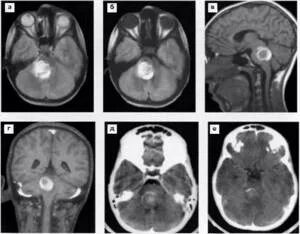

Метастазы в головном мозге мкб